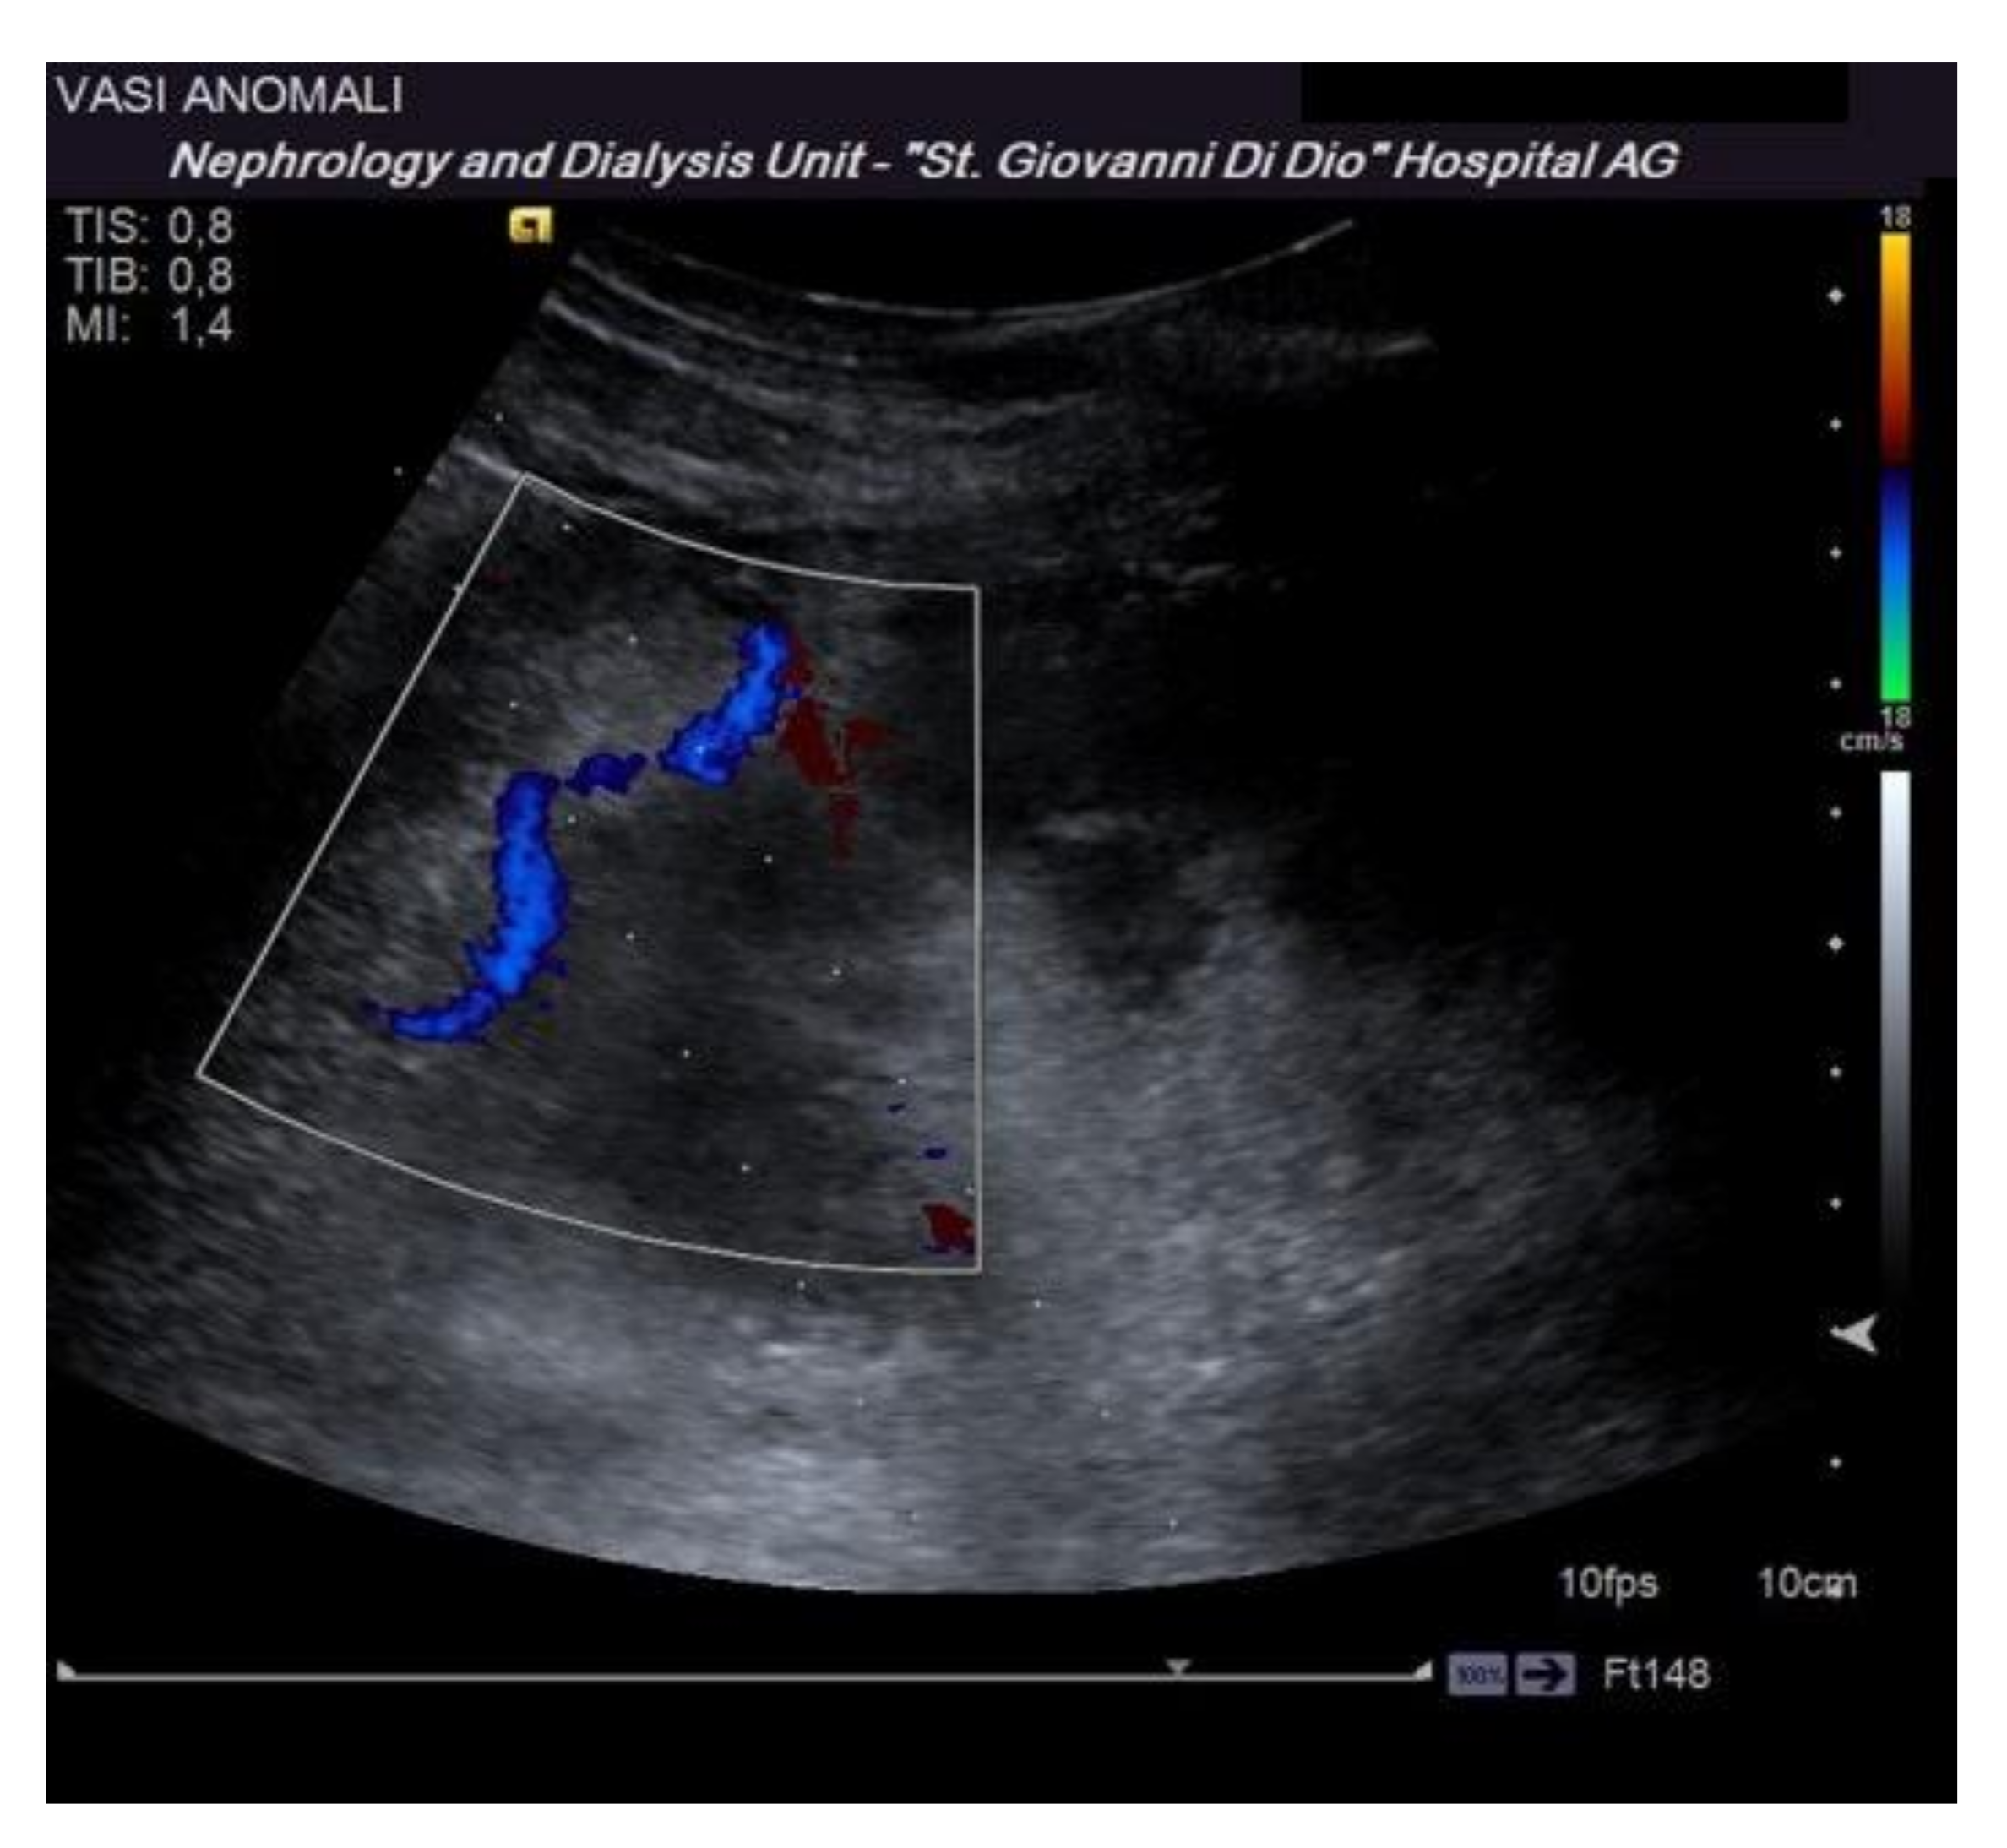

- Granata, A.; Floccari, F.; Ferrantelli, A.; Rotolo, U.; Di Lullo, L.; Fiorini, F.; Logias, F.; Gallieni, M.; Fiore, C.E. Does systematic preliminar colour Doppler study reduce kidney biopsy complication incidence? Int. J. Nephrol. 2011, 2011, 419093. [Google Scholar] [CrossRef] [Green Version]